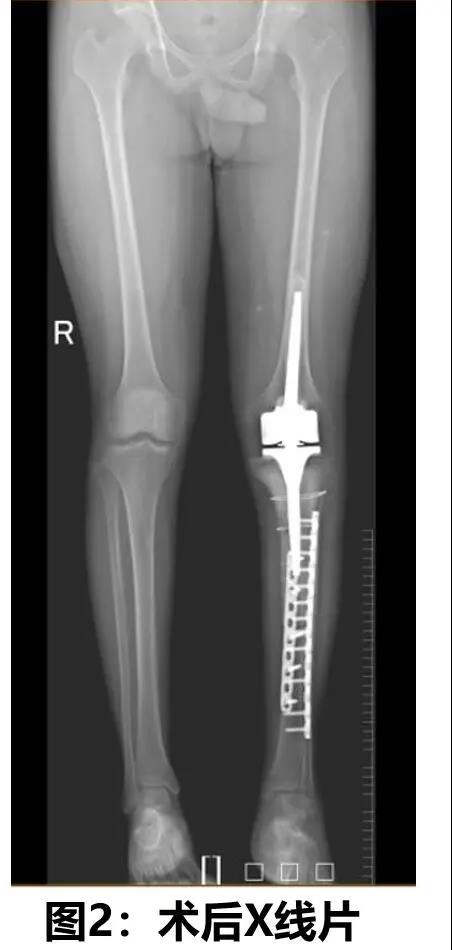

After two rounds of preoperative neoadjuvant chemotherapy and one week of preoperative preparation, the surgery which was led by Dr. Yu Bin, Head of the Department of Orthopedic Trauma of Nanfang Hospital was performed by the Bone Tumor Subspecialty Group in five steps - "left tibia tumor bone resection + liquid nitrogen for cryotherapy treatment + removed tumor bone replantation + tumorous type knee joint prosthetic replacement + dual plate internal fixation of tibia". After eight hours, the surgery was completed smoothly. Twenty days after the surgery, the patient was discharged from the hospital. He will receive further comprehensive treatment in the next step.